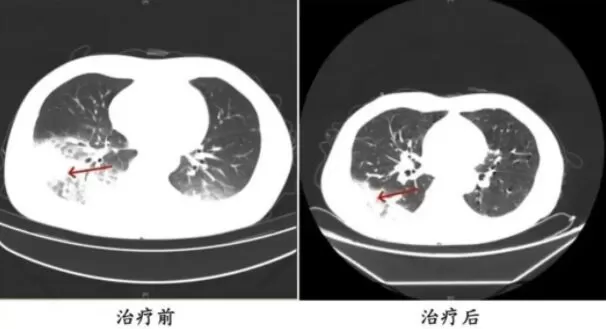

胸部CT显示李先生的左肺已出现大面积白色影像,几乎占据一半肺部。经过肺泡灌洗NGS检测,最终确认“罪魁祸首”是嗜肺军团菌。

d3.webp 李先生肺部治疗前与治疗后的对比